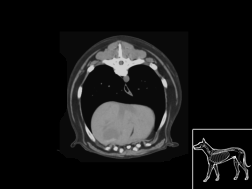

Atlas abdomen du chien SCTO

Scanner tissu osseux

>> 44 coupes

Atlas abdomen du chien SCTM

Scanner tissu mou

>> 43 coupes